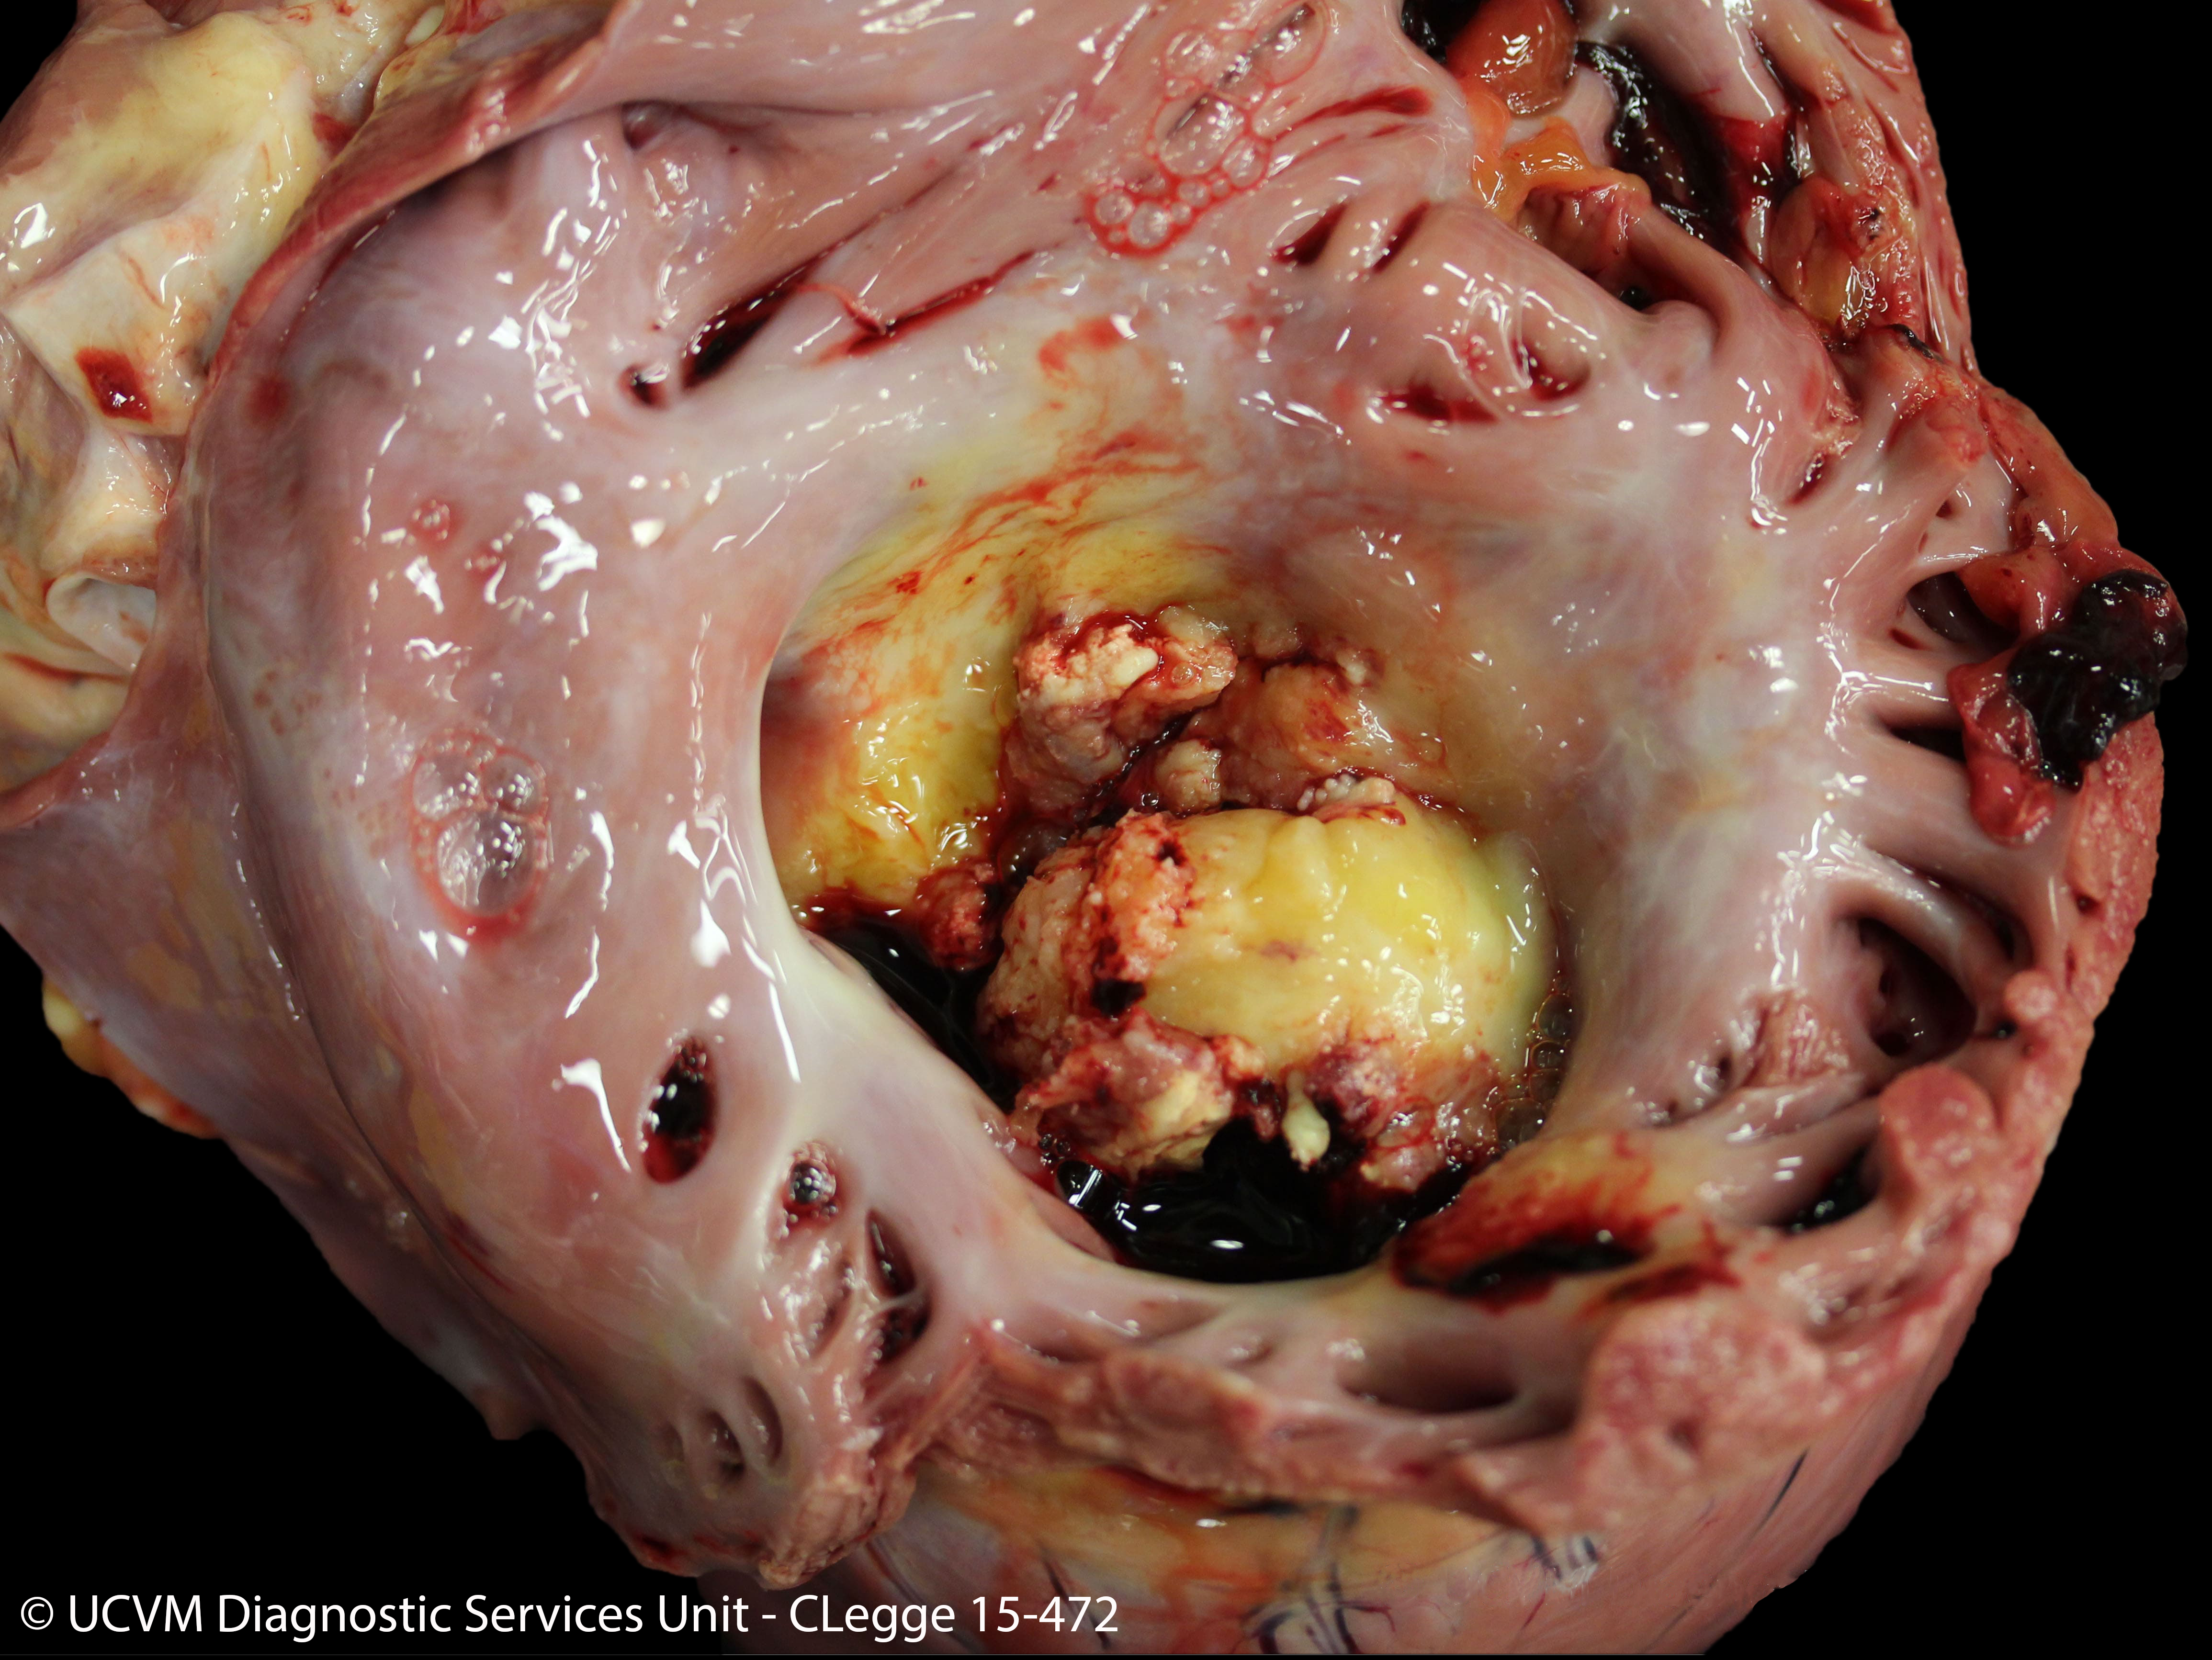

CN: 15-472

Species: Equid, Horse

Heart, right AV valve

Vegetative valvular endocarditis caused by Streptococcus zooepidemicus

Irregular yellow-red or yellow-gray vegetations on the valve leaflets, with underlying ulcerations